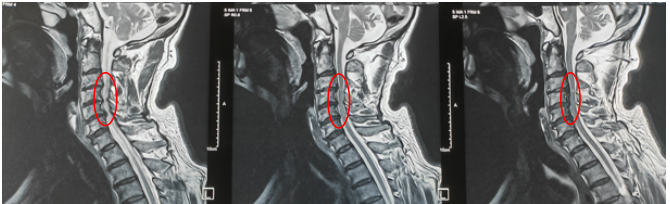

入院后,在胡临教授的带领下,对患者病情进行充分的讨论,诊断为“颈3-6水平椎管狭窄”,有明确手术指征。林大爷得知要手术,内心一直有点忐忑不安,担心自己年龄偏大,无法承受手术的风险……住院的日子里,胡临教授和他的团队成了林大爷最坚实的后盾。他们不仅制定了精细的手术方案——“后入路颈椎双开门椎管减压术”,还像家人一样关心着他的每一个情绪变化。手术前夜,胡临教授来到病房,缓解了大爷的紧张焦虑情绪,像春风一样吹散了大爷心中的阴霾。